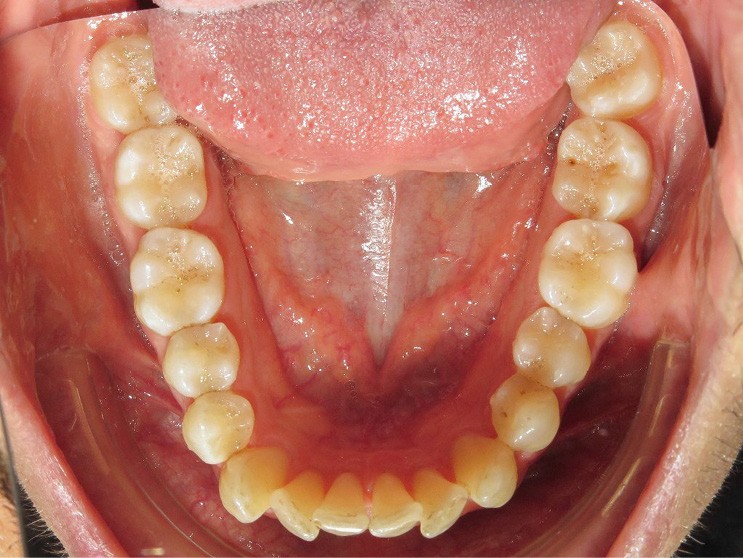

Diagnostic (fig. 1a-i)

Le patient consulte initialement pour des défauts d’alignement. L’examen clinique confirme l’existence d’un encombrement antérieur bimaxillaire, mais révèle aussi la présence d’une Classe II dentaire sévère, d’une exoclusion de la 27 et de troubles parodontaux (peu ou absence de papilles inter-dentaires). Sur le plan squelettique, le patient est relativement équilibré avec un profil harmonieux.